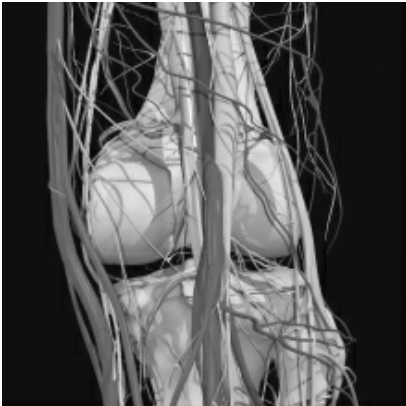

膝关节后侧血管神经

注意:①④⑦点处应避开大隐静脉,②⑤⑧点应避开动、静脉,胫神经,③⑥⑨点应避开腓总神经。1天内保持术区干燥、清洁,适度活动膝关节。依病情治疗,1~3次为一疗程,每次间隔时间为5~7天。